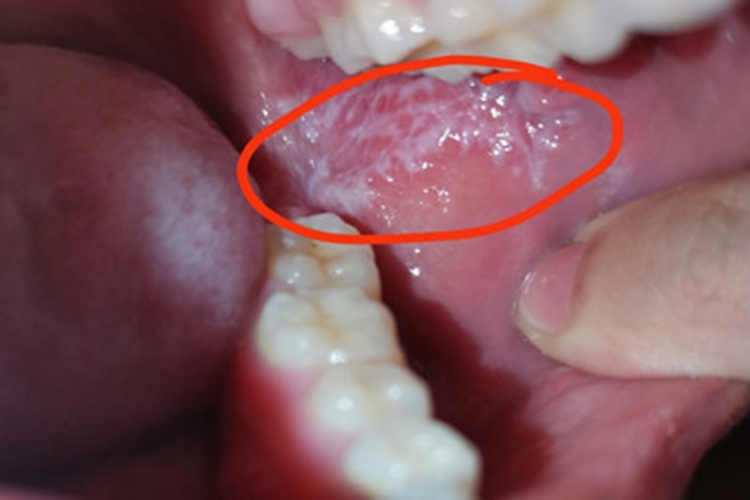

扁平苔藓可累及患者口腔,可表现为口腔内出现白斑,呈不规则状或是网状,周围有暗红色晕,与正常黏膜之间的界线清晰,患者无不适症状。